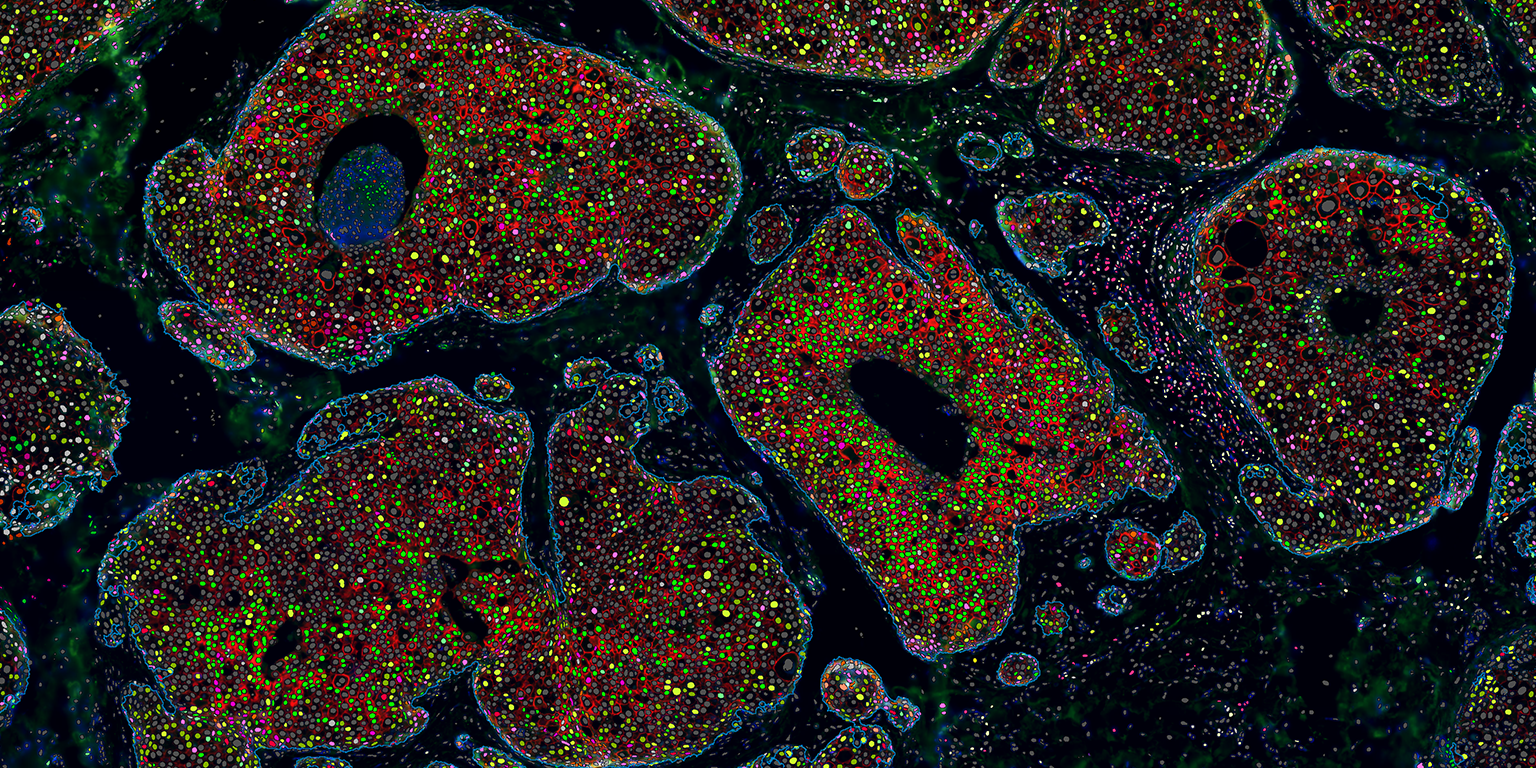

Visiopharm’s pioneering image analysis tools support thousands of scientists, pathologists, and image analysis experts in academic institutions, biopharmaceutical industry, and diagnostic centers. AI-based image analysis and tissue mining tools support research and drug development research worldwide, while CE-IVD APPs support primary diagnostics. With the most advanced and sophisticated artificial intelligence and deep learning, Visiopharm delivers tissue data mining tools, precision results, and workflows.